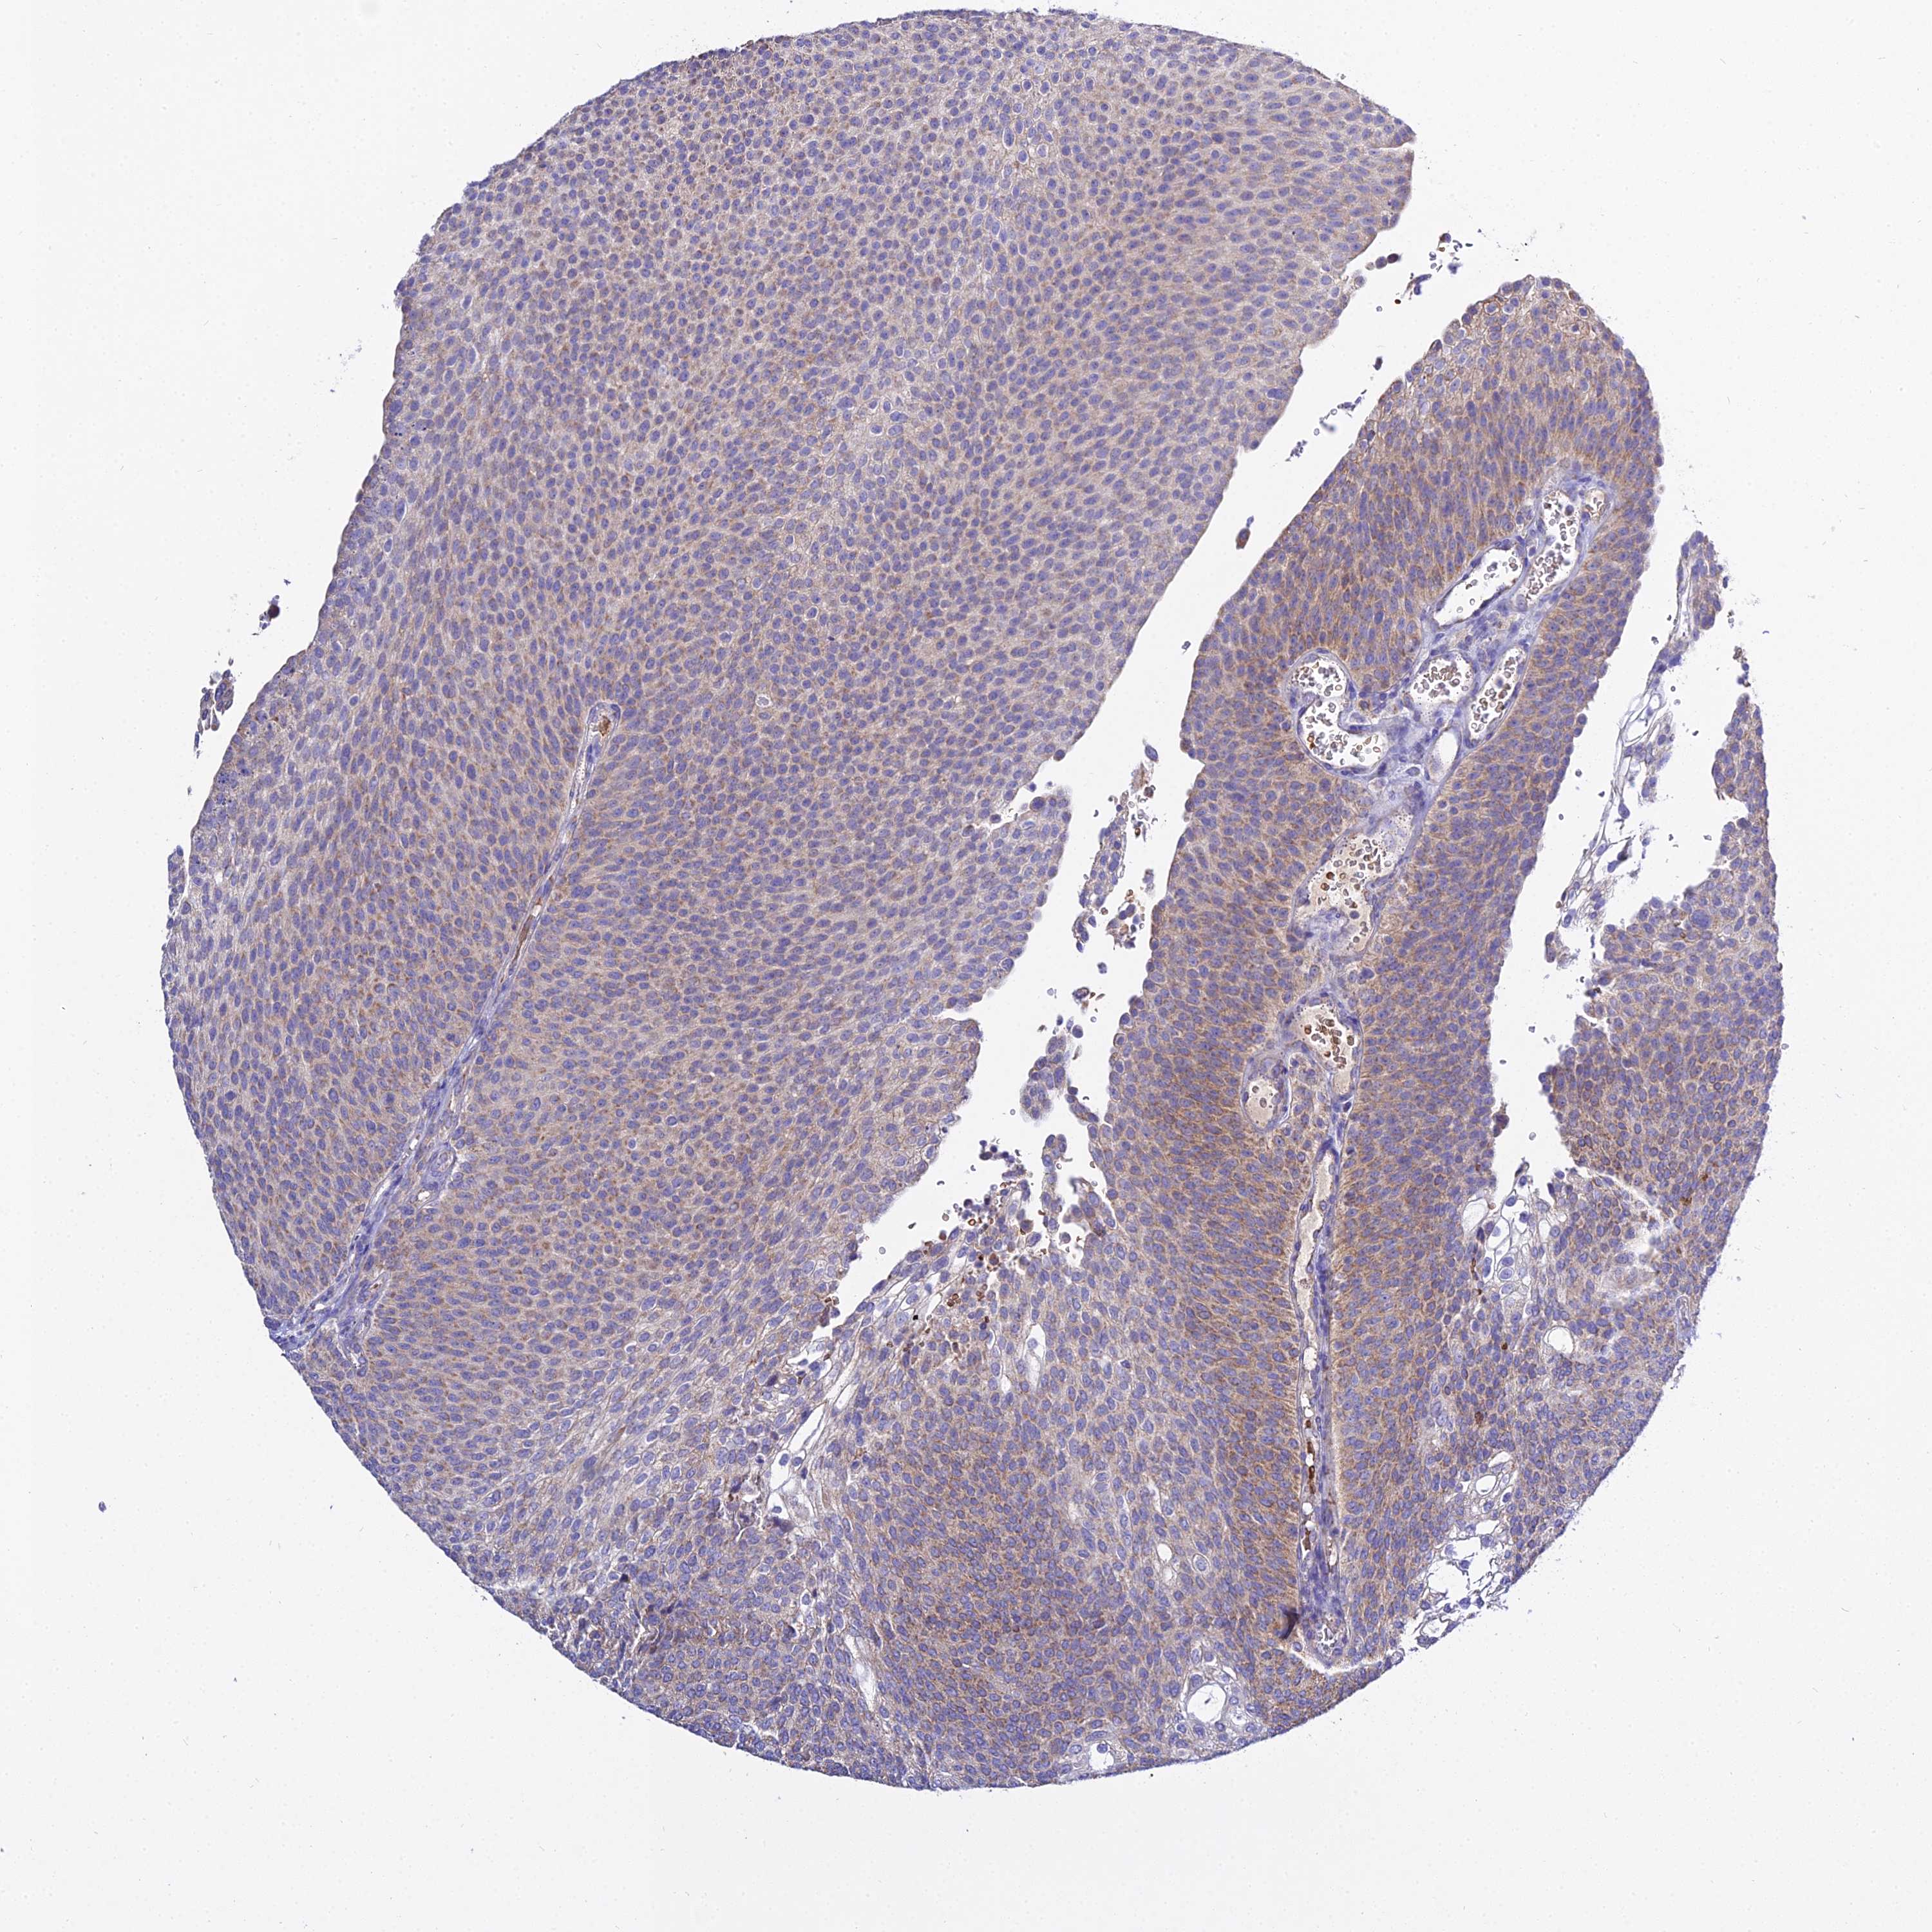

UROTHELIAL CANCER - Protein expressioni

A mouse-over function shows sample information and annotation data. Click on an image to view it in a full screen mode. Samples can be filtered based on level of antibody staining by selecting one or several of the following categories: high, medium, low and not detected. The assay and annotation is described here.

Note that samples used for immunohistochemistry by the Human Protein Atlas do not correspond to samples in the TCGA dataset.

Antibody stainingi

Antibody staining in the annotated cell types in the current human tissue is reported as not detected, low, medium, or high, based on conventional immunohistochemistry profiling in selected tissues. This score is based on the combination of the staining intensity and fraction of stained cells.

Each image is clickable and will lead to virtual microscopy that enables deeper exploration of all samples and also displays staining intensity scores, fraction scores and subcellular localization as well as patient and tissue information for each sample.

Antibody HPA045803

Staining

High

Medium

Low

Not detected

Intensity

Strong

Moderate

Weak

Negative

Quantity

>75%

75%-25%

<25%

None

Location

Nuclear

Cytoplasmic/membranous

Cytoplasmic/membranous,nuclear

Urothelial carcinoma, High grade

Urothelial carcinoma, Low grade